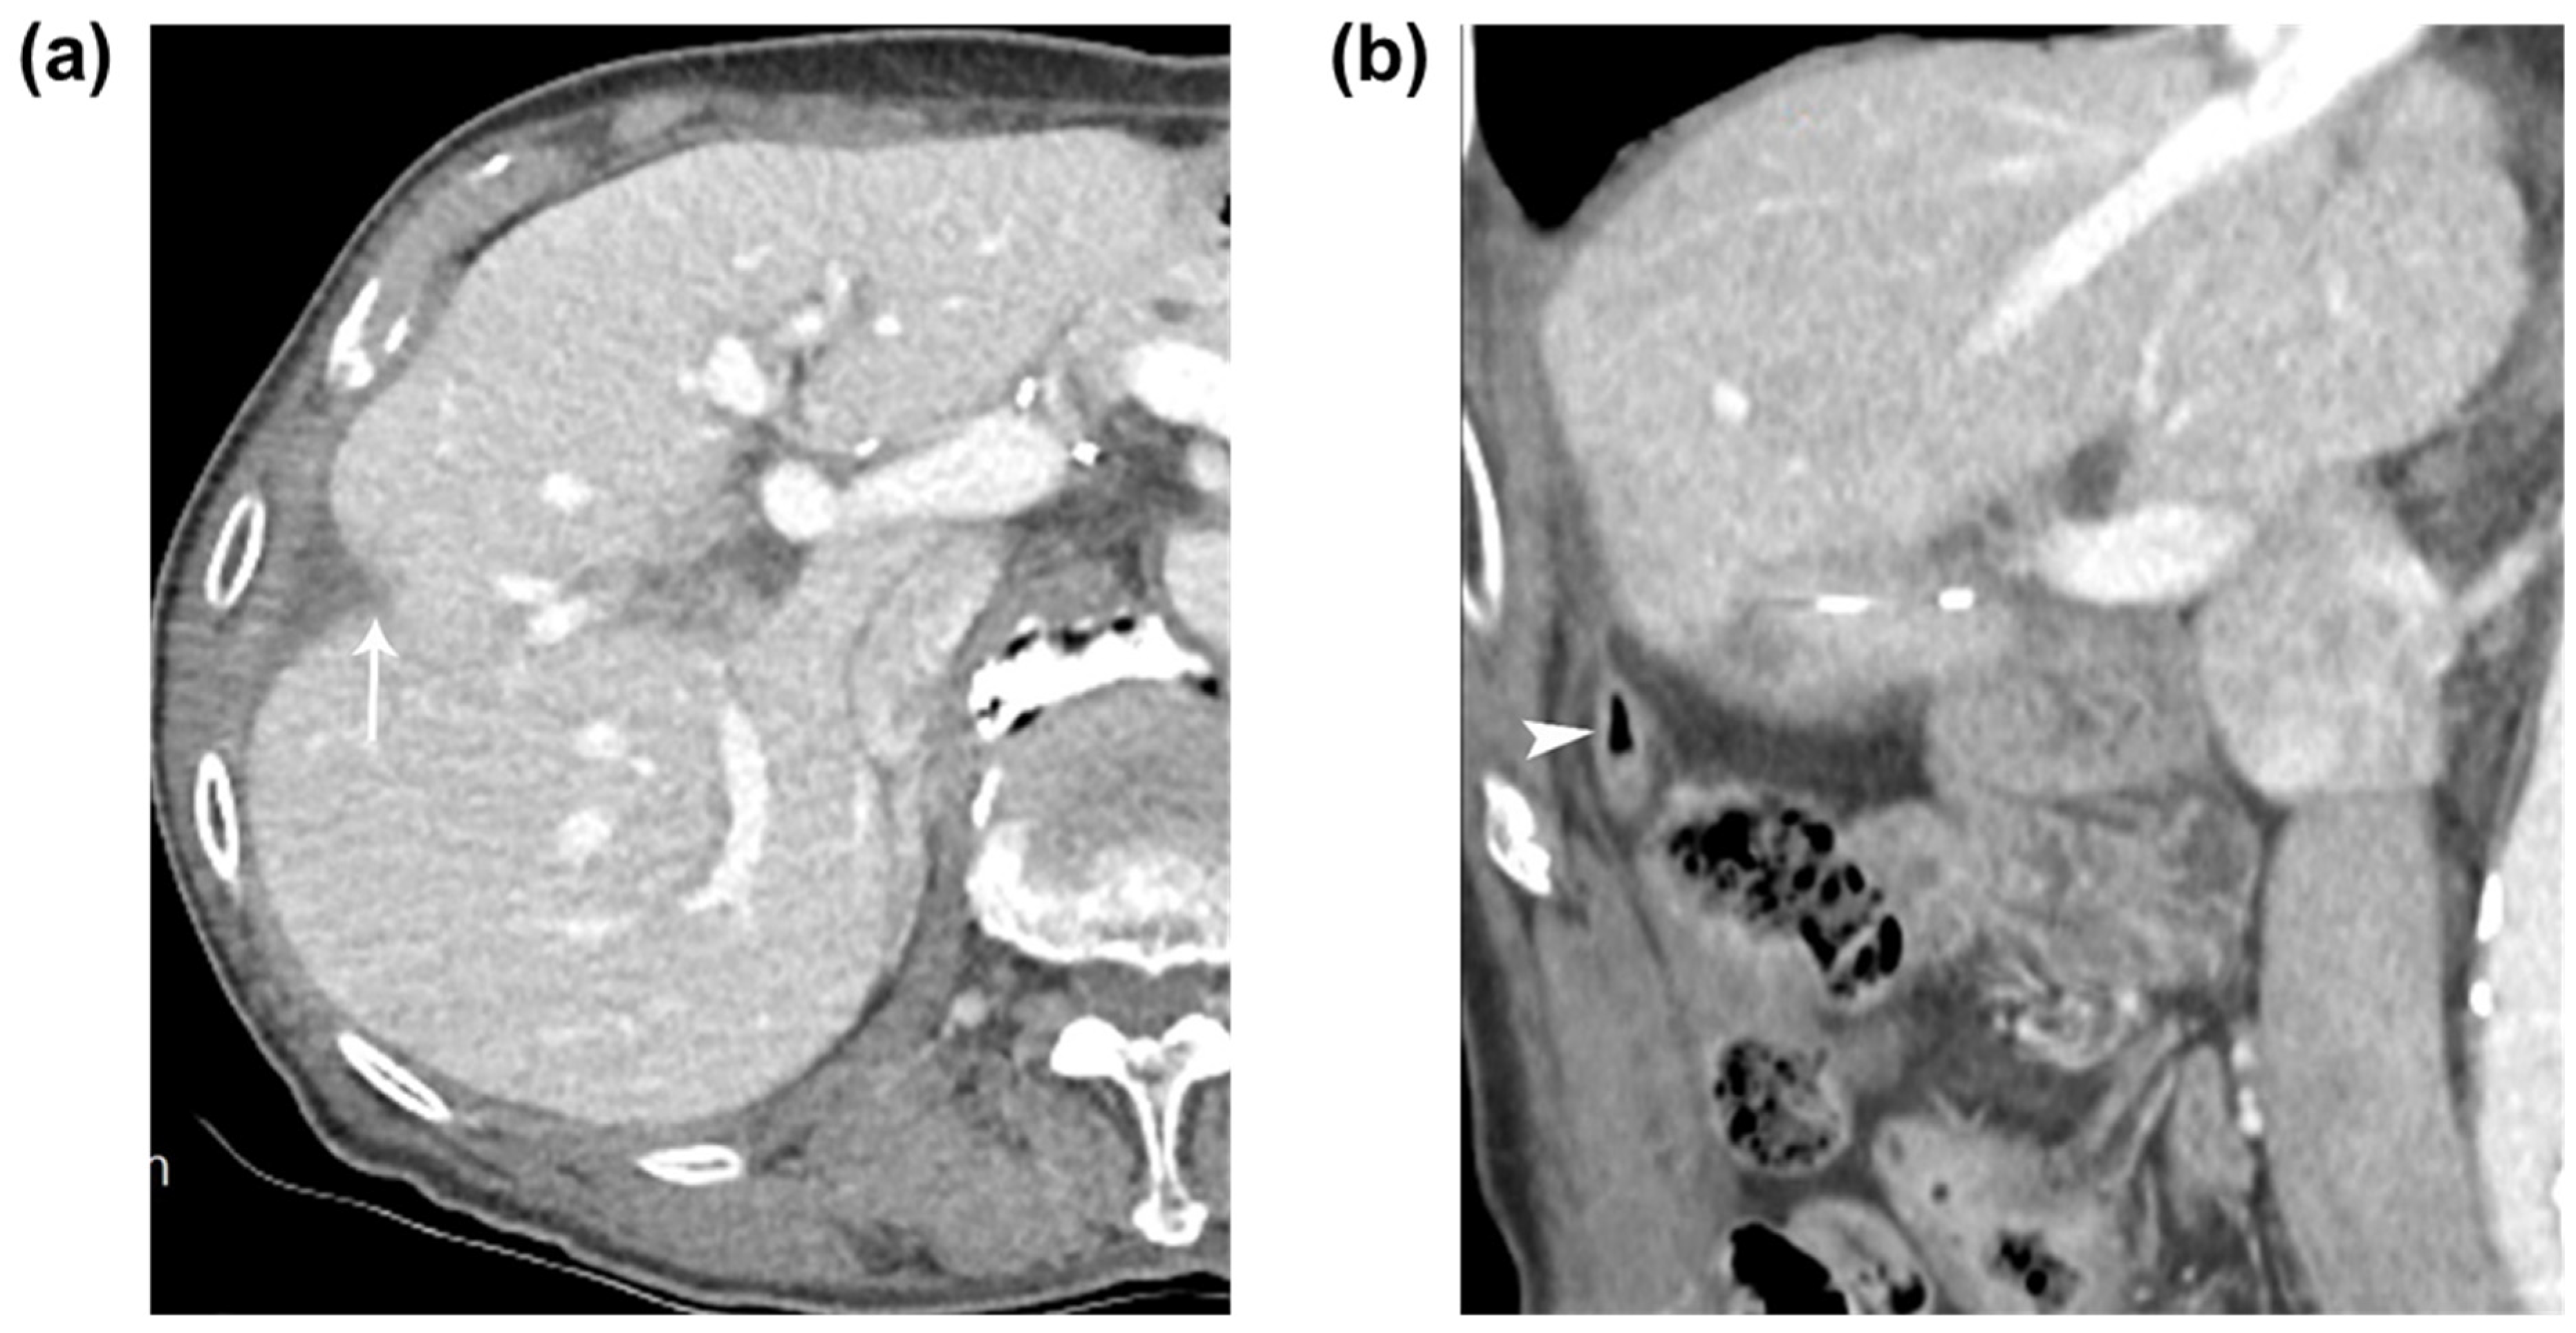

Eight months later, the patient was readmitted to the hospital for an evaluation of right upper abdominal pain. A CT scan revealed a remaining fistulous tract between the ablated zone and the appendiceal tip. The patient was treated with intravenous antibiotics and underwent repeated percutaneous drainage. After 1 month, the patient’s clinical parameters normalized, and a follow-up tubogram showed no communication between the appendix and the ablated zone. A follow-up CT scan showed the involuted RFA zone in segment 5 of the liver without a complete resolution of the abscess and recurrence (Figure 3). The patient underwent regular follow-up for 3 years without recurrence or any complication. Complete resolution of the abscess with a fistula between the previously ablated area and the appendix after 9 months. (a,b) Nine-month follow-up CT images showed the involuted RFA zone (arrow) in segment 5 of the liver and the intact appendix (arrowhead) with a complete resolution of the abscess or fistula. Percutaneous US-guided RFA is an effective treatment which is widely used for the treatment of HCC. The clinical outcome of RFA is influenced by major complications, one of which is thermal injury to non-targeted organs adjacent to the liver tumor. When performing RFA for tumors located in the inferior segment of the liver, such as the adjacent colon, thermal injury can occur [1,2,3,4,5,6]. However, in our case, there was the formation of an abscess or fistula between the appendiceal tip and the RFA zone due to collateral thermal injury that caused appendicitis as the subhepatic appendix was located adjacent to the RFA zone. The typical locations of the cecum and appendix are in the right lower abdomen, but due to anomalies and variations in midgut rotation, they can be located in the left part of the abdominal cavity, below the pylorus, or in the subhepatic space. When the elongation of the proximal colon does not extend sufficiently into the right lower abdomen in Phase III, subhepatic cecum and appendix can occur, which accounts for approximately 6% of all cases [7]. The positional variations of the appendix, such as its location and length, can lead to different clinical manifestations, inflammatory patterns, and complications, including abdominal pain [8,9]. In our case, the appendix and cecum were located in the right upper subhepatic space due to a variation in Phase III, with the appendix positioned in the caudocranial direction, traversing from the subhepatic space to the perihepatic space in the form of an inverse cecum that was relatively short and located posteriorly to the ascending colon. Additionally, a previous pylorus-preserving pancreaticoduodenectomy, which required the dissection of the right colon for duodenum and SMV exposure, likely caused adhesions between the cecum, appendix, and subhepatic space. Despite pre-treatment hydrodissection, collateral thermal injury occurred, leading to the formation of an abscess between the ablated zone and the appendiceal tip. The treatment for appendicitis typically involves appendectomy using laparoscopy as a primary option but in our case, surgical intervention was difficult due to adhesions caused by previous surgeries. Several articles suggest that nonoperative management could be considered for patients with perforated appendicitis [10,11]. Nonoperative management may be suitable for patients presenting with localized abdominal pain and a stable condition but not for those with diffuse abdominal pain or a deteriorating condition [12]. In our case, we started with nonoperative management using antibiotics and planned to perform frequent imaging follow-ups. After confirming the formation of an abscess via CT, we additionally performed percutaneous drainage guided by imaging. It is important to note that recurrence is most common within the first 6 months of follow-up in patients with perforated appendicitis who undergo nonoperative management, with a reported rate of recurrent appendicitis of 12.4% during the follow-up period [10]. Before performing RFA, imaging should be used to confirm the presence of heat-vulnerable organs around the tumor and to check for any anomalies or variations in the organs. Especially in cases like ours, in which the tumor is located in the inferior segment of the right hemiliver and there is a history of previous abdominal surgery, the position of not only the colon but also the cecum and appendix should be confirmed. To minimize thermal injury before the procedure, hydrodissection or the infusion of artificial ascites can be an effective strategy for successful RFA. However, despite aggressive pre-treatment, careful observation and diagnosis are important considering the possibility of fistula formation or abscess formation in the ablated zone and adjacent organs when thermal injury is suspected upon immediate follow-up CT. Nonoperative management should also be considered depending on the situation of the disease.